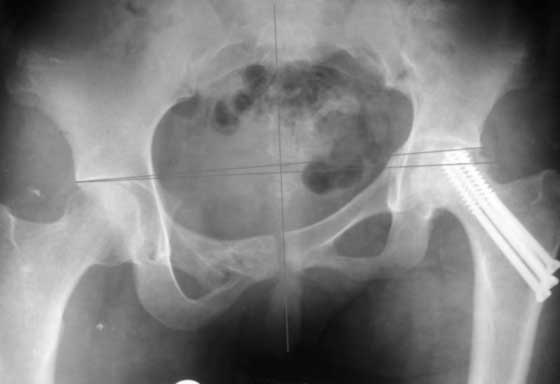

Привет всем. Укорочение за счет таза не менее 3см.

В задних отделах таза ничего не изменилось (см снимок в аппарате). Картинка кажется лучше за счет оссификата в седалищной вырезке от задней колонны к кп сочленению.

Привет, Макс. Не торопись, посмотри внимательно на истинную картину. Толстая стрелка указывает на нижний край смещенного кп сочленения.

Поэтому считаю, что Принять какое-либо решение без кт и дополнительных проекций неразумно.

Представленный случай - перелом таза типа С сросшийся со смещением. Укорочение будет не менее 4 см ( Р- гр в краниальной проекции покажет это). Начинать надо с таза.

Доброго времени суток. Согласен с предыдущими авторами, что необходимы стандартные проекции рентгенограмм и КТ (желательно с 3D). Обратите внимание, что рентгенограммы получились с небольшим поворотом вправо (по естественным причинам) и косо. Последнее можно скорректировать поворотом изображения по часовой стрелке на 2,6 градусов (для большей наглядности).

Вероятнее всего, что укорочение конечности за счет таза составит не более 3 см.,

Это хорошо видно на прилагаемой картине

По первым снимкам имеется сложная травма с переломом ацетабулума (видна линия перелома в задней колонне) и таза с ипсилатеральным переломом шейки. Не удалось репонировать крестцово-подвздошное сочленение, и смещение с ротацией осталось, особенно в верхней ветви лонной кости. Клинические снимки подтверждают остаточную деформацию и укорочение конечности за счет таза.